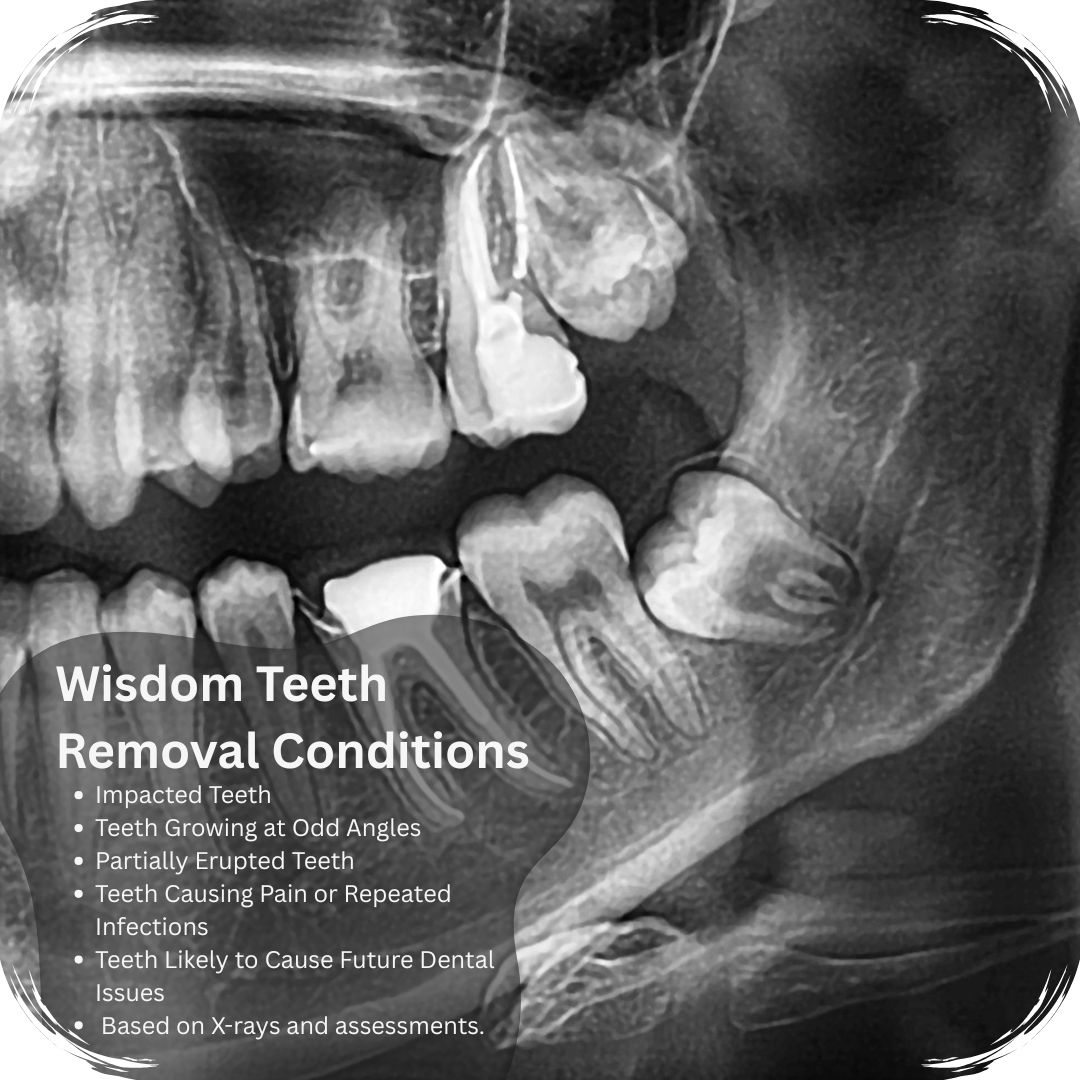

Dentists typically suggest removal when wisdom teeth are:

- Impacted: When teeth can’t emerge normally due to lack of space

- Growing at odd angles: Potentially damaging adjacent teeth

- Partially erupted: Creating pockets where bacteria can thrive

- Causing pain or repeated infections: Indicating problematic development

- Likely to cause future dental issues: Based on X-rays and assessments